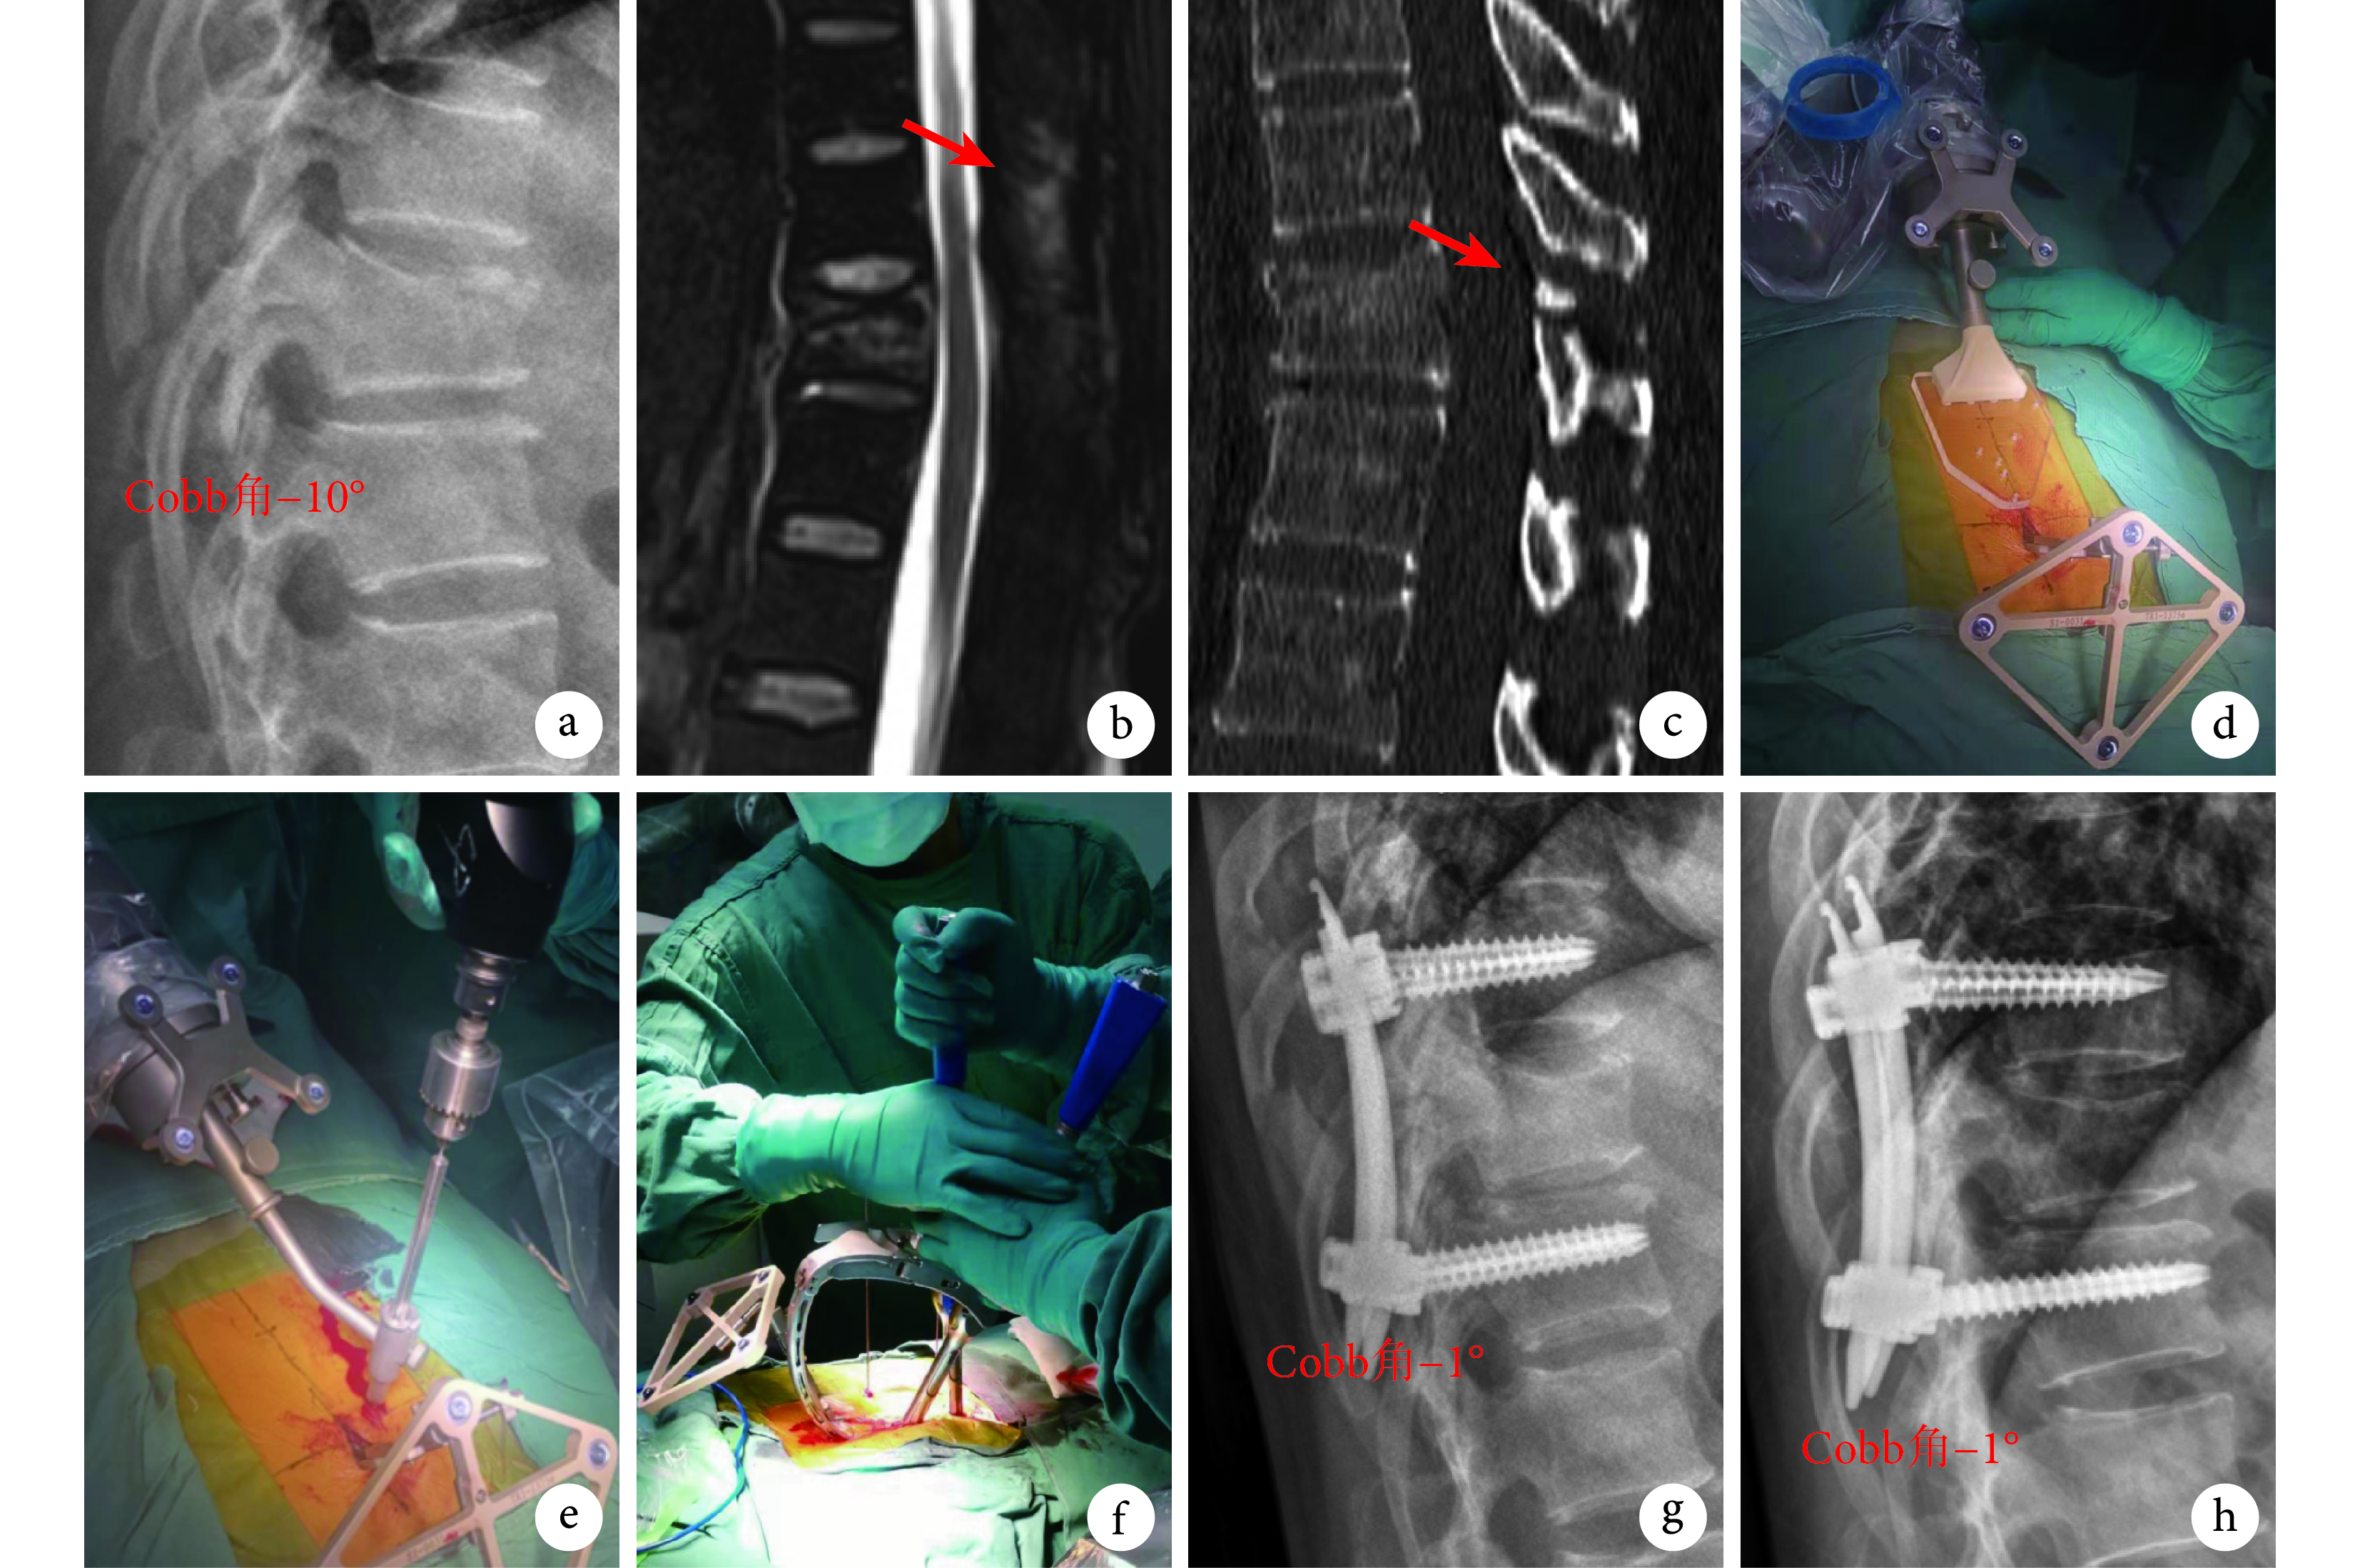

a. 術前側位 X 線片;b. 術前 MRI 示后柱韌帶復合體損傷(箭頭);c. 術前 CT 示 T11 椎板骨折(箭頭);d. 在 T10 棘突上安裝示蹤器及定位標尺;e. 機器人輔助定位下植入導針;f. 植入空心椎弓根螺釘和鈦棒;g. 術后 3 d 側位 X 線片示椎間高度及后凸 Cobb 角復位良好;h. 術后 10 個月側位 X 線片示椎間高度及后凸 Cobb 角維持良好

Figure1. A 48-year-old female patient with T11 vertebral compression fracture and posterior ligamentous complex injury by traffic accident injury in minimally invasive groupa. Preoperative lateral X-ray film; b. Preoperative MRI, showed posterior ligamentous complex injury (arrow); c. Preoperative CT scan, showed laminar fracture of T11 (arrow); d. Tracer and positioning ruler were installed on the spinous process of T10; e. Inserting guide wire with robot-assisted; f. Implanting cannulated pedicle screw and titanium rod; g. Lateral X-ray film at 3 days after operation, showed the segment height and Cobb angle of segment kyphosis were well recovered; h. Lateral X-ray film at 10 months after operation, showed the segment height and Cobb angle of segment kyphosis were well maintained